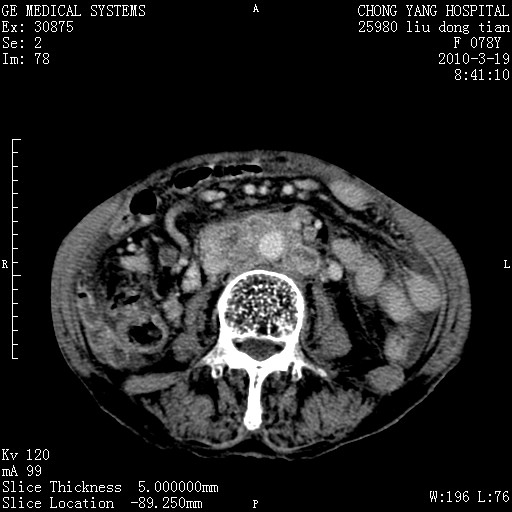

标题: CT25199:F 78Y 腹胀半年 消瘦乏力 [打印本页]

胆囊壁增厚并明显强化,胆囊癌伴多发转移瘤可能性大,淋巴瘤不除外,右肾囊肿,胸腹水.

考虑nhl,肝、脾、腹膜腔及腹膜后多发淋巴结受侵,腹水,右肾囊肿,慢性胆囊炎,右侧少量胸腔积液。

胰头有肿块形成,胰头ca伴肝脾、腹膜腹膜后转移

胆囊有软组织影有强化,支持胆囊癌,肝脾、腹膜后淋巴结转移。

nhl的淋巴结多围绕主动脉,而且主动脉会移位,所以不考虑nhl。

分开来讲:肝左叶、尾叶病灶有不均强化像肝癌;

脾脏病灶无强化,像多发囊肿或淋巴管瘤,不除外淋巴瘤(低强化);

胆囊增生性病变:胆囊癌,腺肌增生症,慢性胆囊炎;

肝门、胰腺头、腹膜后多个团块: 淋巴瘤,转移;

腔静脉肝内段细小有无布加可能?

一元论最好了 淋巴瘤所致改变; 胆囊癌转移不像,胆囊周围肝组织清晰,肝癌淋巴结转移?三元论都不止。

最后报的胰头癌多发转移,脾脏单独考虑囊肿或淋巴管瘤。